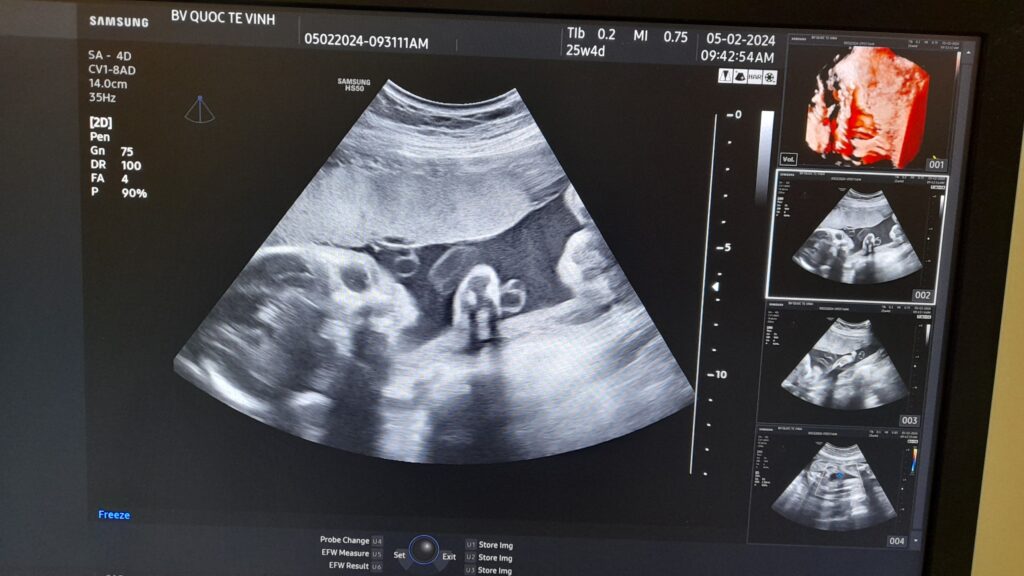

Một trường hợp siêu âm thai phát hiện dây rốn một động mạch tại Bệnh viện Hoàn Mỹ Vinh

siêu âm phát hiện dây rốn một động mạch

Đây là một trường hợp thai phụ đến Bệnh viện Hoàn Mỹ Vinh để khám và sàng lọc dị tật thai nhi bằng siêu âm 4D. Trong quá trình siêu âm phát hiện thấy dây rốn của bé có 2 mạch máu, một tĩnh mạch, một động mạch. Thai nhi đã được bác sĩ kiểm tra kĩ để phát hiện các dị tật kèm theo, may mắn là em bé chỉ bị dây rốn một động mạch đơn độc, cân nặng và các chỉ số đều trong giới hạn tăng trưởng bình thường theo ISOUGH, tiên lượng tốt. Bác sĩ đã giải thích cho thai phụ, tư vấn và hướng dẫn thai phụ khám thai định kỳ để theo dõi sự phát triển của bé.